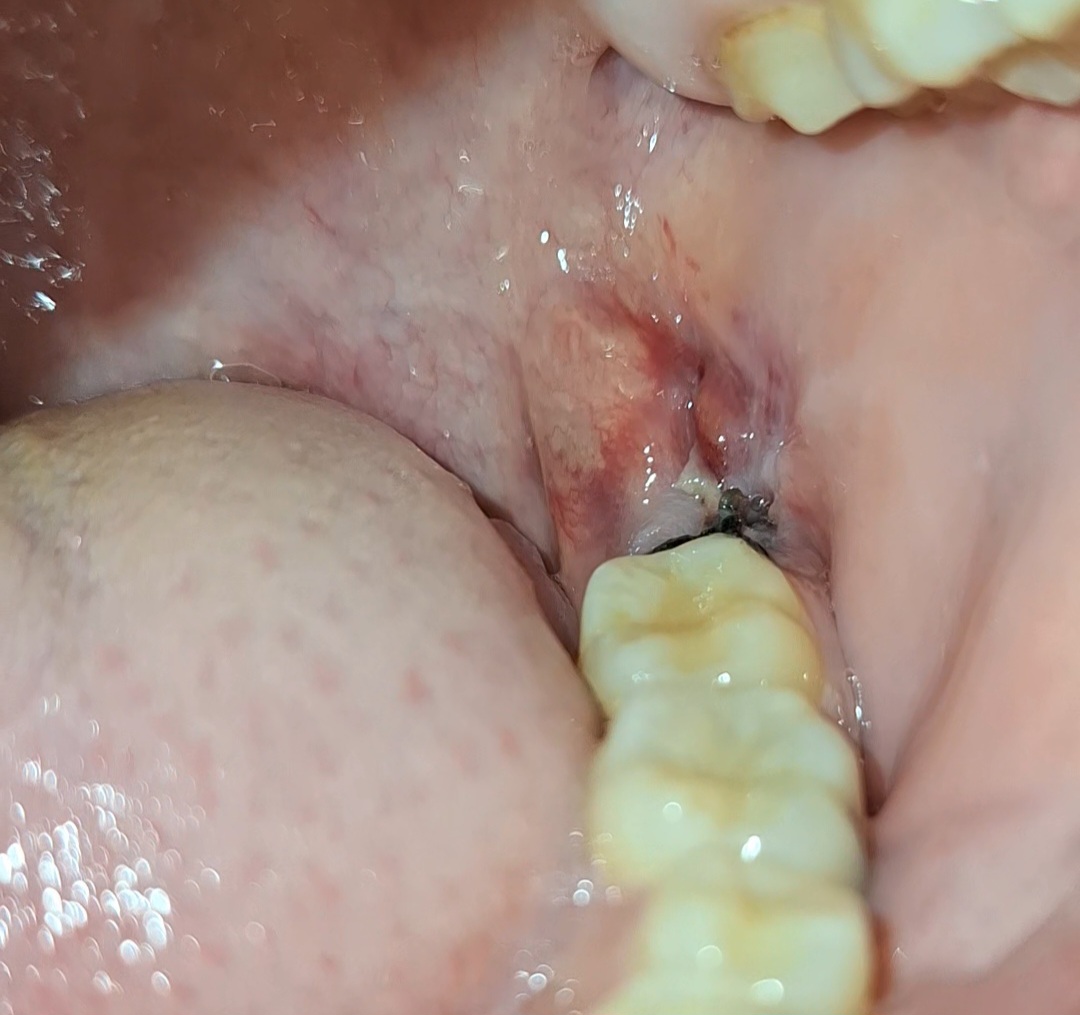

แผลหลังจากผ่าฟันคุดมาได้2วันแบบนี้ปกติมั้ย

ไปผ่าฟันคุดมาได้2วันแล้วแผลเป็นแบบนี้ มีกลิ่นปากนิดหน่อย แต่มันไม่ปวดไม่เจ็บมาก มันปกติใช่มั้ยแต่เห็นพอแผลเป็นแบบนี้เลยทำให้กังวลมากๆ (ToT)

ผ่าฟันคุดมาเมื่อวันที่ 2 มิถุนา 68 แผลมาแผลลมากเพราะอยู่ใกล้เส้นประสาทแต่ไม่มีอาการชา กังวลว่าแผลจะติดเชื้อหรือเป็นหนองมั้ย เพราะผ่านมา 2 วันแล้ว ยังปวดมากอยู่เลย แถมยังมีเลือดซิบๆอยู่ตรงเหงือกตามรูป